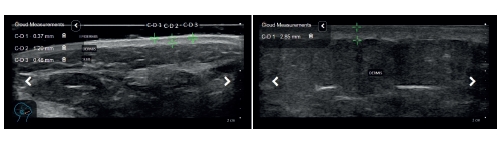

En el mundo de la cosmética avanzada, la tecnología desempeña un papel clave en la evaluación y desarrollo de productos innovadores. Uno de los aspectos más estudiados en dermatología y estética es el impacto del envejecimiento y el estrés oxidativo en la piel. Para comprender mejor estos efectos, los profesionales se apoyan en herramientas de diagnóstico de alta precisión como el Scanner Clarius PAL HD, capaz de analizar estructuras esenciales como la unión dermoepidérmica (DEJ) y la banda subepidérmica de baja ecogenicidad (SLEB).

Por otro lado, la banda subepidérmica de baja ecogenicidad (SLEB) es un indicador clave en estudios de ultrasonido dermatológico. Esta banda, visible mediante el Scanner Clarius PAL HD, muestra alteraciones en la piel relacionadas con el envejecimiento y el estrés oxidativo. Un engrosamiento de la SLEB puede indicar inflamación y daño dérmico, mientras que su adelgazamiento sugiere pérdida de colágeno y elastina, lo que lleva a una reducción en la capacidad de regeneración cutánea.

El Scanner Clarius PAL HD es una herramienta de última generación que permite a los profesionales de la estética y dermatología obtener imágenes de ultrasonido de alta resolución para evaluar con precisión el estado del DEJ y la SLEB. Su tecnología inalámbrica y su facilidad de uso lo convierten en un dispositivo esencial para estudios clínicos y optimización de tratamientos cosméticos.